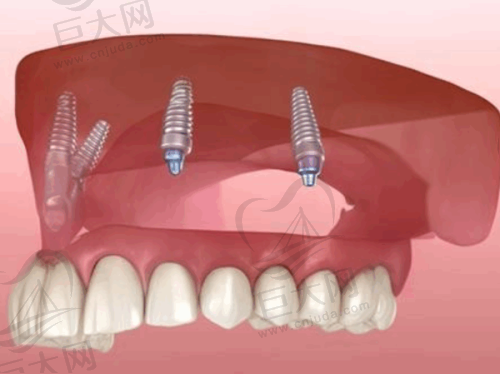

种植牙技术方面,即刻负重种植可以当天拔牙、当天种牙,大大缩短了治疗周期;All - on - 4/6技术半口仅需4 - 6颗植体,适合骨量不足的患者;亲骨种植针对骨质疏松人群,生物相容性更佳,能减少植骨需求。